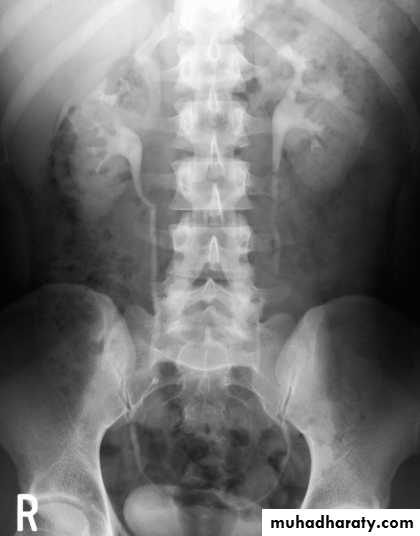

Intravenous Pyelogram (IVU)

The IVU series consist of:1-KUB film…To identify any calcification like stones or nephrocalcinosis.

2-Post contrast film…

• Check that the kidneys are in their normal positions (the left is usually higher than the right)

• Identify renal outlines…For any bulge or indentation.

• Measure the renal length (10-16 cm) these are higher than those for renal size on ultrasound.

• Calyces should be evenly distributed and symmetrical.

• Its shape is normally cupped , when dilated becomes clubbed.

• The normal renal pelvis is funnel shaped

• The ureters are usually seen in only part of their length on any one film of an IVU.

• The bladder is centrally located and should be smooth in outlines.

Often show normal smooth indentations from above due to uterus or sigmoid colon.

-After micturition the bladder should be empty apart from little contrast trapped in the folded mucosa.